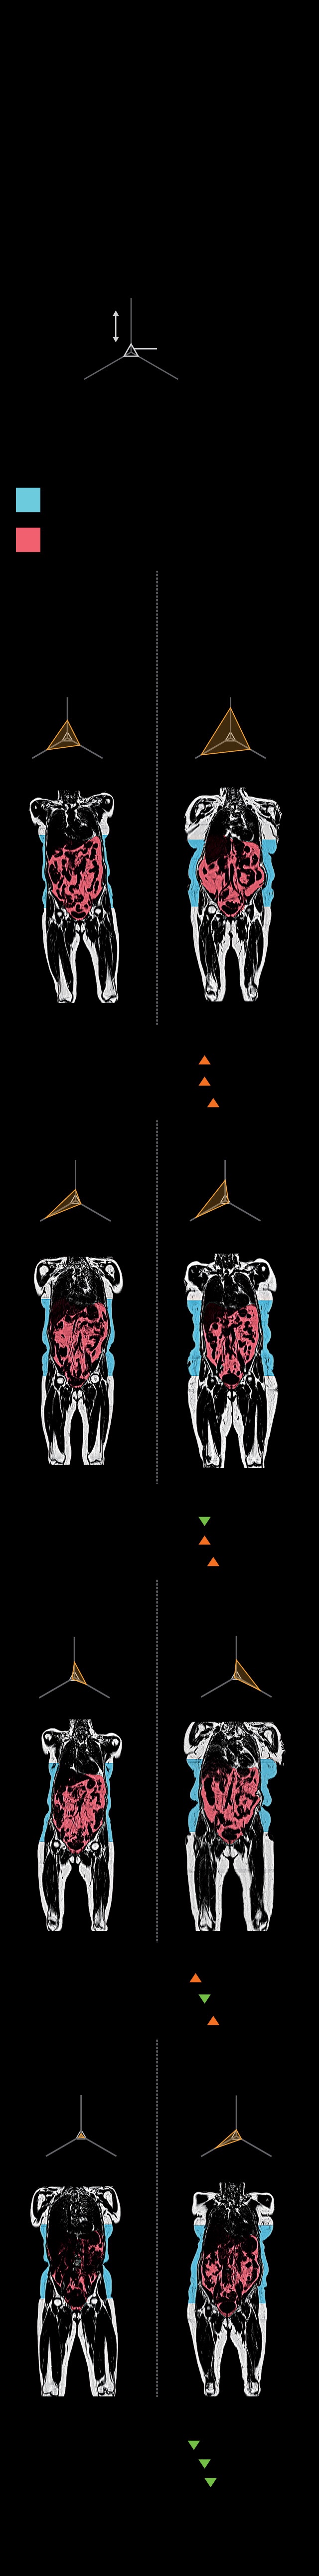

MRIs performed on some Biobank participants create 3D images that show subcutaneous fat under the skin in blue and visceral fat around the organs in red. Visceral fat has been linked to diseases. (See graphic below.)

AMRA MEDICAL AB

IT’S NOT THE FAT—

IT’S WHERE IT’S AT

Body mass index (BMI) has long been used to

measure obesity and health risk, yet it can’t

explain why an overweight person might be

healthy or why a seemingly healthy person

might get heart disease or diabetes. New MRI

data show that when it comes to fat, where it’s

located matters most.

FAT DISTRIBUTION

Subcutaneous fat, under the skin, can be less

harmful than visceral fat, found around the or-

gans. Visceral, liver, and muscle fat (orange

lines, below) are linked to metabolic diseases.

Subcutaneous

Visceral

Obese

Four women with

a BMI of 32 but

different fat

distribution

Normal weight

Four women with a

BMI of 24 but differ-

ent fat distribution

Probability of:

High

Heart disease:

Type 2 diabetes:

Metabolic disease:

Low